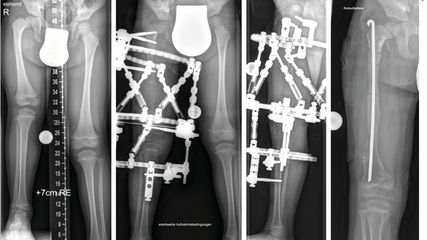

Abb. 2: Präoperative (a+b) sowie postoperative Bildgebung (c+d) eines 5-jährigen Patienten mit CPT

Rezente Klassifikation berücksichtigt die Integrität der Tibia und Fibula, die Stellung der distalen Fibula in der Gelenksgabel sowie das Vorhandensein knöcherner Defekte.11 Sowohl konservative Therapie zur Frakturvermeidung als auch operative Verfahren zur Korrektur der Fehlstellung stehen zur Verfügung: Orthesen, Anlage eines externen Fixateurs, intramedulläre Marknagelung, Transfer einer vaskularisierten Fibula oder Durchführung einer sogenannten Cross-Union (X-Union). Abbildung 2b zeigt hierzu den Fall einer Cross-Union-Operation mit Resektion der Pseudoarthrose, guter Knochenbrücke zwischen Tibia und Fibula (Cross-Union), Stabilisierung der Tibia mit intramedullärem Teleskopnagel und Platte, Stabilisierung der Fibula mit Bohrdraht (Abb.2c,d).11,12